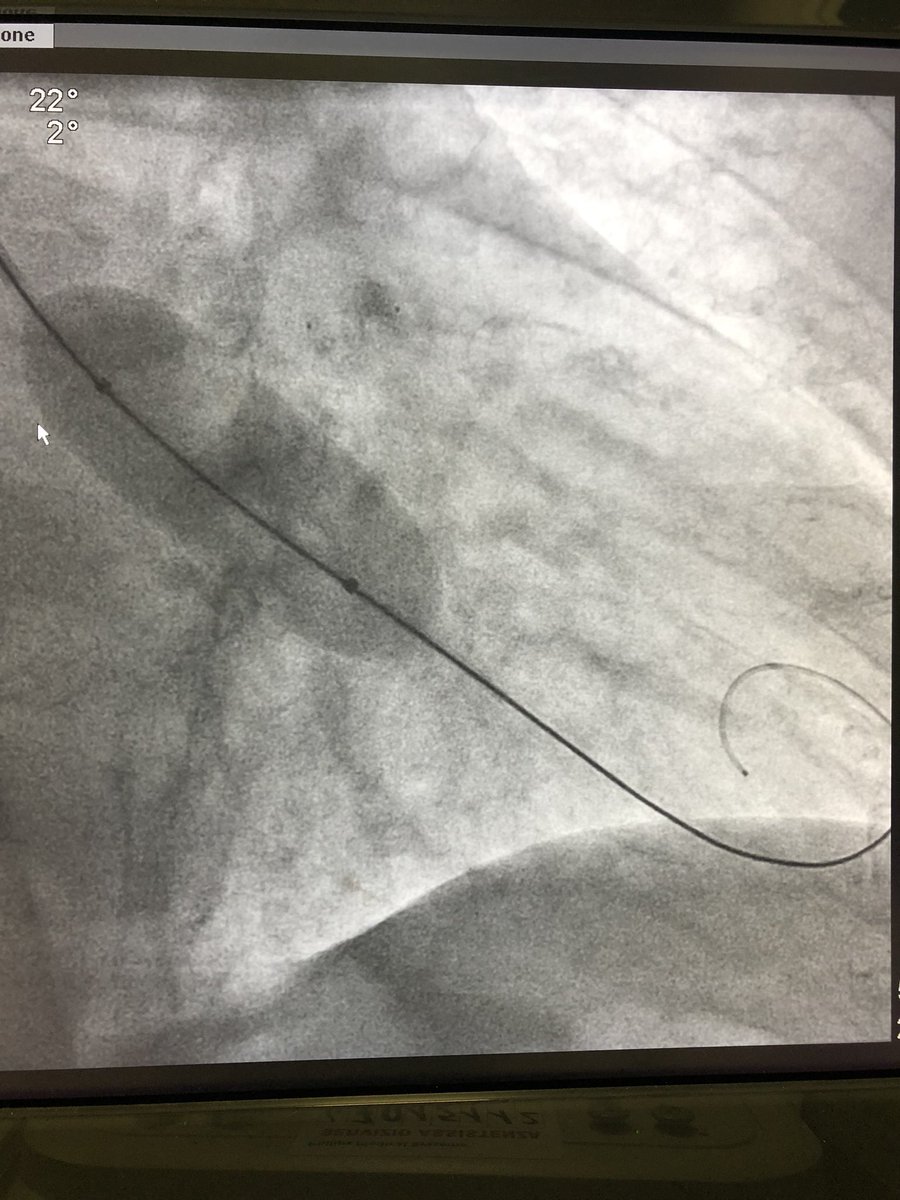

That’s a 10F sheath for a trans-radial

#BAV bridge-to-decision in a 93 yo man with severe#AS and#MR. 3 dilatations with a 20mm and 2 with the 23mm, minimal pain at removal of the 20mm

#EAPCI@radialfirst@SVRaoMD@ferdikiem@skat_ctpic.twitter.com/GMwUDNHGEo